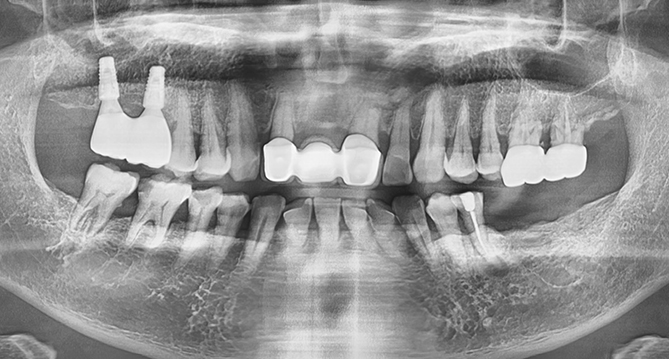

연세새빛치과 상악동거상임플란트 사례

연세새빛치과 전악 임플란트 사례